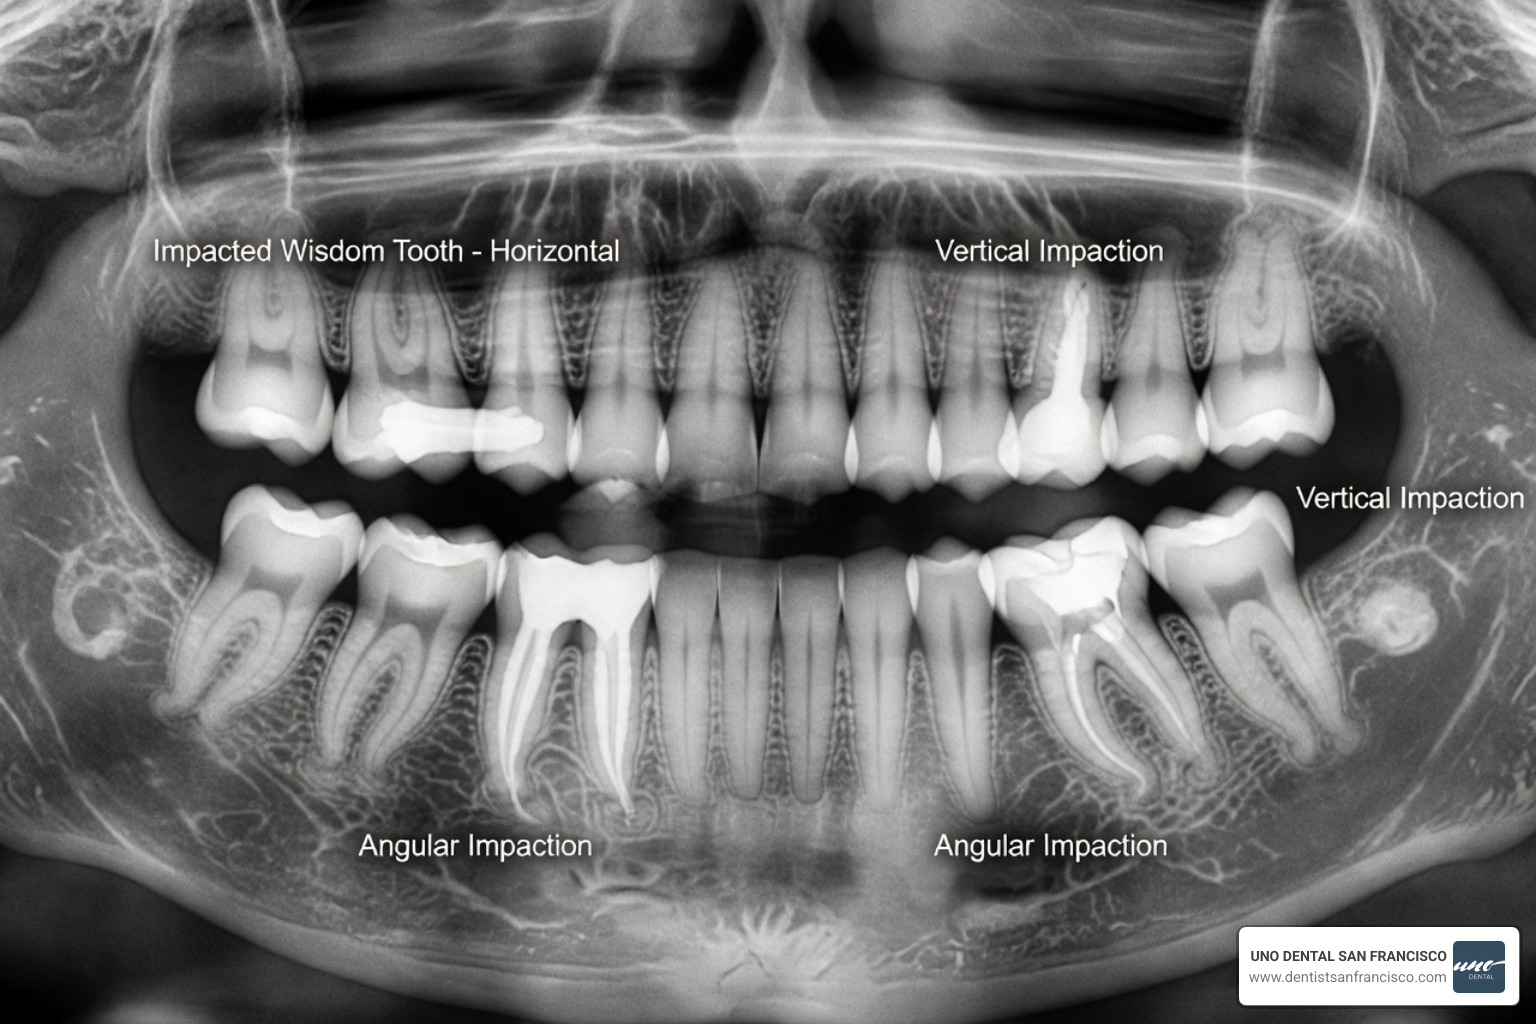

Wisdom teeth — your third molars — are the final set of teeth to emerge, typically between the ages of 17 and 25. Research indicates that approximately 90% of individuals will experience at least one impacted wisdom tooth in their lifetime. Impacted teeth are those that remain trapped beneath the gum line or grow at an angle, necessitating a more involved removal process that can often induce anxiety.

If your wisdom teeth are fully erupted and correctly aligned, local anesthesia may be sufficient. However, if the teeth are impacted—meaning they are trapped under bone or gum tissue—the procedure becomes more complex. In cases such as a "coronectomy," where only the crown is removed to protect a nearby nerve, we often suggest higher levels of sedation to ensure you remain perfectly still. You can find more impacted wisdom tooth surgery details here.